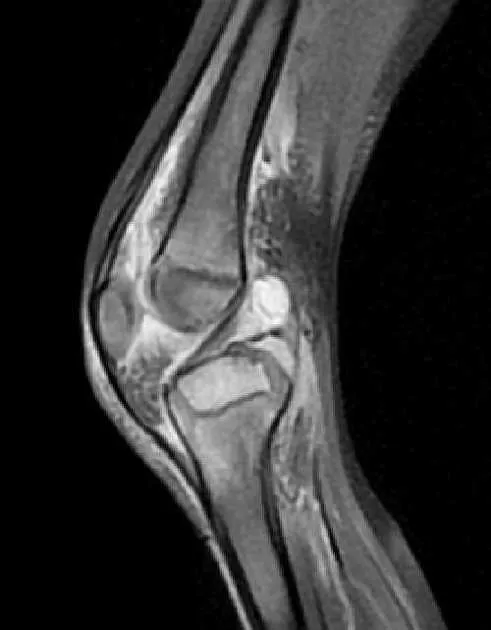

- MRI: Most sensitive & specific for early diagnosis & extent.

- T1: ↓ signal in marrow.

- T2/STIR: ↑ signal (edema).

- Post-contrast: Enhancing phlegmon/abscess.

⭐ MRI is the imaging modality of choice for detecting osteomyelitis in its early stages (within 24-48 hrs) and for delineating soft tissue involvement.